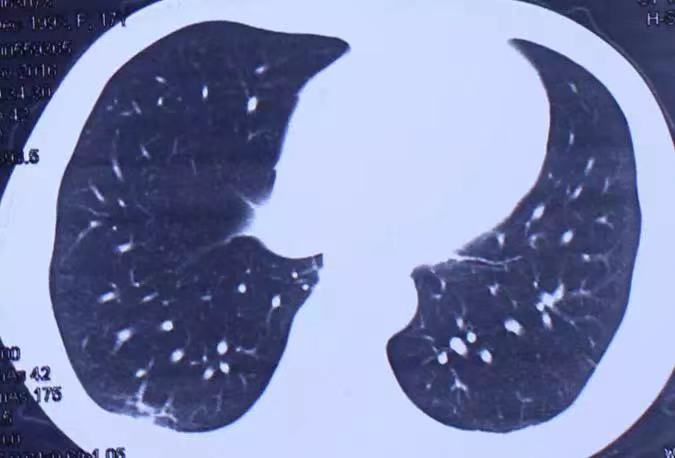

图片来源网络从影像学上来看,肺纤维化的肺窗表现多为毛玻璃状或云絮状阴影。人体吸气时,进入肺泡的氧气穿过肺泡壁以及缠绕在肺泡壁上的毛细血管进入血液;血液流动将氧气带到身体的各个组织细胞。而组织细胞利用氧气分解有机物,产生的二氧化碳进入血液;当血液流经肺部毛细血管时,血液中的二氧化碳穿过毛细血管壁进入肺泡,再通过呼气排出体外,这是我们正常呼吸的过程。而肺纤维化意味着呼吸的氧气和二氧化碳需要穿过的“肺间质”变得“奇厚无比”。